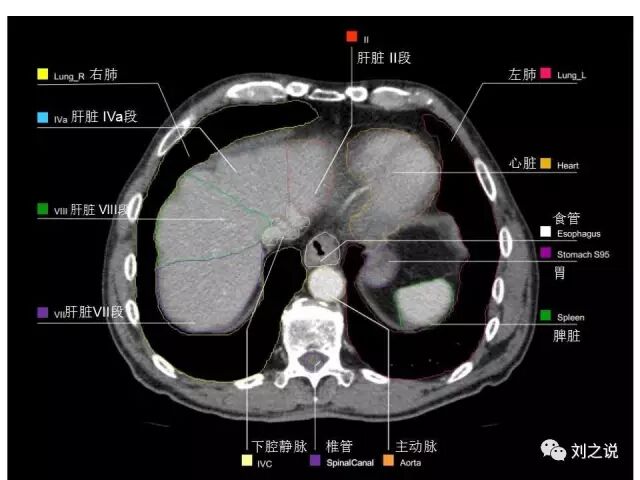

参考RTOG共识和3D-body解剖。

来源:刘之说